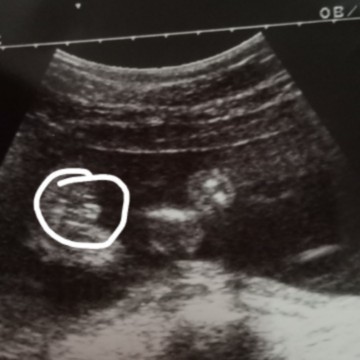

เป็นกลีบแบบนี้ใช่ลูกสาวไหมคะขอถามแม่ๆค่ะ

เหมือนจะเป็นไข่น้องรึป่าวคะแม่ 😅

บ้านนี้เปนแบบนี้ค่ะ เปนแหลมๆๆ

บ้านนี้เมษาจ้าอันนั้นภาพตอน22วีคจ้าตอนนี้30วีคแล้ว